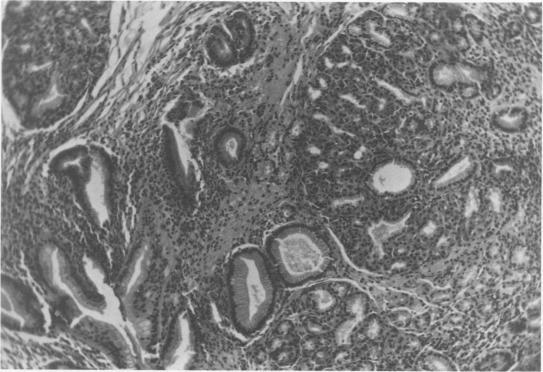

The operations of Nissen, Hill, and Belsey are adequate in controlling esophaegeal reflux in the majority of patients. In a small percentage however, objective and subjective evidence of esophagitis persists in spite of repeated operations to restore lower esophageal sphincter competency. These failures are then usually treated by operative procedures of great magnitude involving organ interposition. Repeated antireflux operations directed to the gastroesophageal area may in some instances result in impairment of blood supply with an increased risk of both esophageal and gastric fistulae. In the past many observers have felt that reflux esophagitis resulted solely from the effects of acid-pepsin secretions bathing the distal esophagus. Recently experimental and clinical data have indicated the importance of duodenal contents in the etiology and perpetuation of reflux esophagitis. During a recent two year period, 6 patients with persistent reflux esophagitis uncontrolled by repeated antireflux procedures have been seen on our service. These 6 patients, underwent 12 unsuccessful antireflux operations elsewhere. Three of the 6 patients had also been subjected to vagotomy-antrectomy for a coexisting duodenal ulcer. A marked lowering of gastric acidity took place but esophageal reflux and esophagitis persisted. These three patients were treated on our service by takedown of the Billroth I anastomosis, closure of the duodenal stump and diversion of the duodenal contents into a Roux-en-Y limb. Three other patients who had undergone unsuccessful antireflux procedures alone were subjected to antral resection, Roux-en-Y diversion and transthoracid vagotomy. This simplified appraoch to the treatment of persistent esophageal reflux uncontrolled by repeated antireflux procedures has given satisfactory results. The operation should be considered when technical considerations preclude further surgical attempts to perform another effective antireflux operation. Total duodenal diversion should, however, not be considered as the primary operation for the patient suffering from reflux esophagitis. However, in circumstances discussed above this direct approach appears preferable to major resectional procedures.